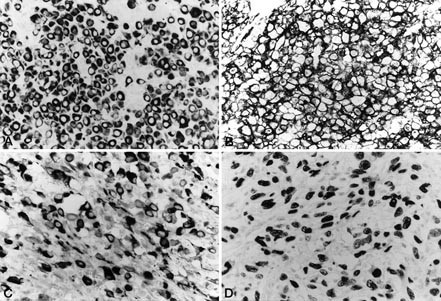

The immunohistochemical results are summarized in Table 3. All 20 cases (100%) showed immunoreactivity for both vimentin and cytokeratin (Fig. 5A). The rhabdoid cytoplasmic inclusions stained variably for vimentin and cytokeratin. EMA was positive in 17 tumors (85%), which displayed moderate to intense cell membrane-based reactivity for EMA. Nine lesions (45%) gave a focal to diffuse membranous positive reaction for CD34 (Fig. 5B). Likewise, focal membranous staining for CD99 (MIC2) was observed in five (25%) lesions. Focal cytoplasmic staining for muscle markers, either desmin or α-smooth muscle actin (SMA), was observed in three (15%) lesions. Twelve cases (60%) were focally positive for other markers, such as S-100 protein, neurofilament, neuron-specific enolase, synaptophysin, and CD56 (N-CAM) (Fig. 5C). Sixteen tumors (80%) yielded positive results for p53 (Fig. 5D). Muscle-specific actin (HHF35), myogenin, CD31, gp100 protein (HMB-45), and chromogranin A were negative in all cases.